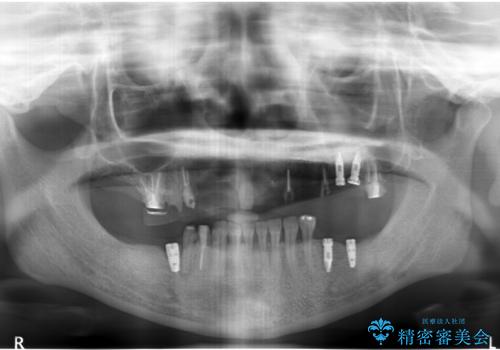

- 痛くて噛めない、これまでだましだまし治療をしてきたがこれを機にすべてきっちりと治したい、口の中の悩みを解決したいと来院されました。

抜歯や歯周病治療、欠損補綴を含め、全顎的な治療を計画・提案します。

(他Drからの引き継ぎ [治療中] の状態より担当)